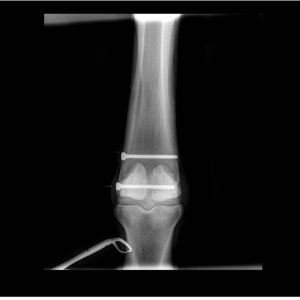

X rays had showed that 402/403 had pulp horn caries with periapical infection, they were dead, so needed to be extracted.

The structure pointed to is a drainage tract, which shows that the infection had been present long enough for it to develop 😳. The problem was first spotted by the vet dentist when he came on a referral visit for another issue which had been noted by the EDT, to fill infundibular caries in 109/110.

After a slow start, and her breath absolutely stank for weeks as the remaining infection drained out, it has healed up really well.